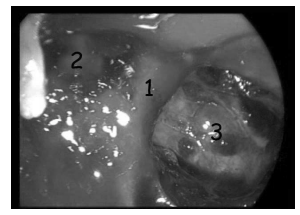

VI нерв, иногда в виде нескольких ветвей, попадает в кавернозный синус из Дореллова канала, далее проходит медиальнее Меккелевой полости и продолжается далее в переднем отделе кавернозного синуса, обычно располагаясь книзу и латеральнее внутренней сонной артерии (рис. 3).

Рис. 3. Пространственное расположение черепных нервов в области боковой стенки кавернозного синуса справа. Пинцетом приподнята первая (лобная) ветвь тройничного нерва (V1) и под ним, в полости кавернозного синуса, латерально от внутренней сонной артерии (ica) расположен отводящий нерв (VI)

В полости кавернозного синуса от ВСА отходят несколько артериальных стволов, наиболее постоянным из которых являются менинго-гипофизарный и нижне-боковой (рис. 5).

Рис. 5. Латероселлярное пространство (анатомический препарат): А — вид с помощью 0º эндоскопа; Б — вид с помощью 45º эндоскопа; 1 — кавернозный сегмент ВСА; 2 — гипофиз; 3 — скат; 4 — симпатическое нервное сплетение ВСА; 5 — нижне-боковой артериальный ствол; Б — ганглий тройничного нерва; 7 — менинго-гипофизарный артериальный ствол; III — глазодвигательный нерв; VI — отводящий нерв; V1 — глазной нерв (первая ветвь тройничного нерва); V2 — верхнечелюстной нерв (вторая ветвь тройничного нерва); стрелкой указано место входа отводящего нерва в полость кавернозного синуса из канала Дорелло.

Отводящий нерв входит в кавернозный синус из канала Дорелло и обычно располагается латеральнее ВСА на уровне верхнего края глазного нерва. Стоит отметить, что сосудистое сплетение ВСА, поднимаясь вдоль паракливального отдела ВСА, доходит до отводящего нерва, что может являться ориентиром для обнаружения VI ч.м.н. при осуществлении транссфеноидального доступа к кавернозному синусу через его передне-нижние отделы (рис. 5).